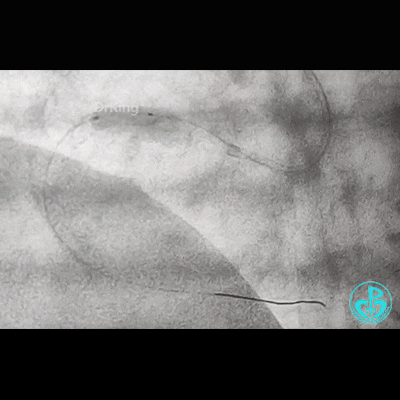

调整GC,重进导丝,先用1.5mm球囊,2.0mm球囊,3.5mm球囊……完成后扩!

此时,鞘管外GC已经扭曲,更换JR 4.0,看右冠开口。

反复操作GC,疑似右冠开口已经夹层,此时心电图无异常!

补3.5×12mm支架一枚。